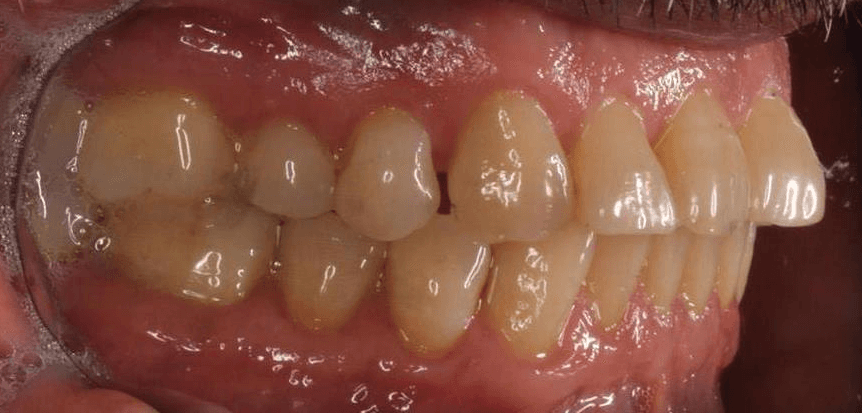

Initial treatment

INTRAORAL